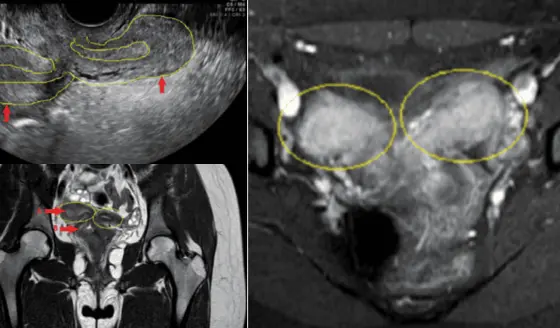

La perforación septal permitió el drenaje parcial pero insuficiente del contenido menstrual. Esta clasificación tiene implicaciones terapéuticas directas, siendo la resección quirúrgica completa del tabique obstructivo (marsupialización) el tratamiento definitivo.